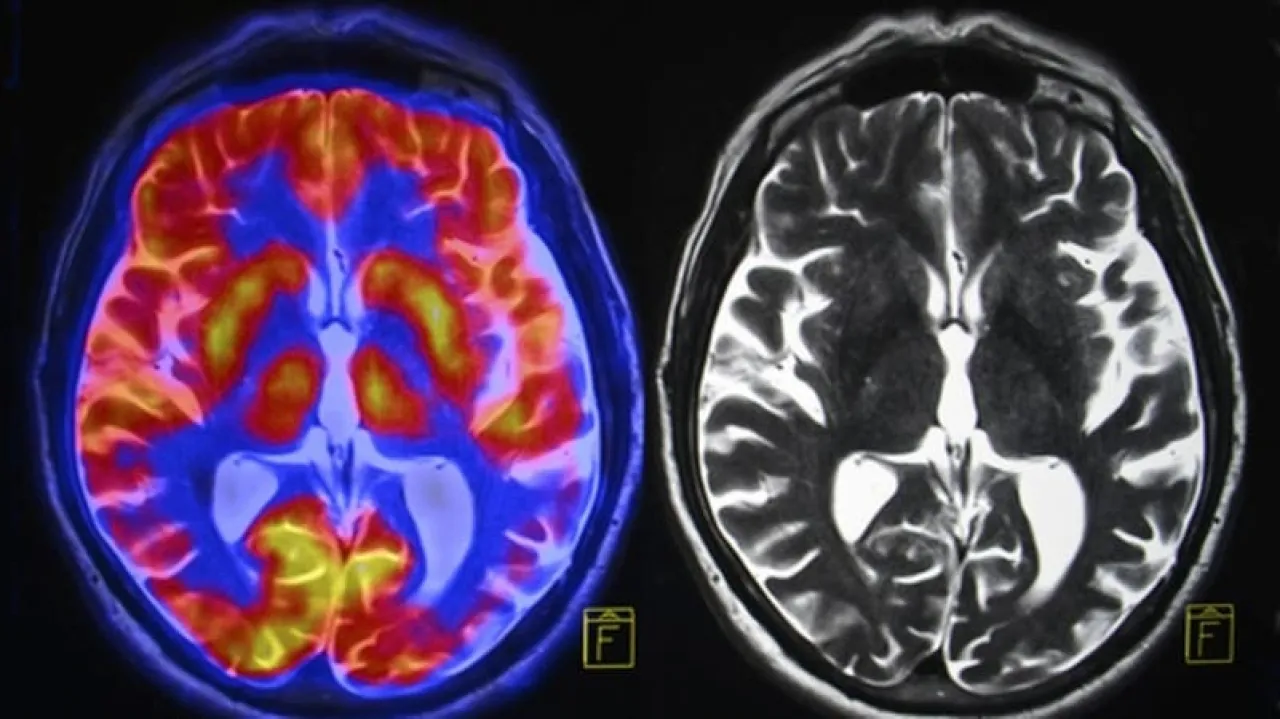

طوّر فريق من الباحثين معيارًا للشيخوخة البيولوجية يعتمد على تصوير الدماغ بالرنين المغناطيسي. ويقول فريق الباحثين إن هذه الأداة قادرة على التنبؤ بمخاطر إصابة الفرد المستقبلية بضعف الإدراك والخرف والأمراض المزمنة مثل أمراض القلب والضعف البدني والوفاة المبكرة.

لتطوير أداتهم، حلل الفريق صور الرنين المغناطيسي للدماغ المأخوذة من هذه المجموعة في سن 45 عامًا، وعالجوا البيانات المتعلقة ببنية الدماغ - حجم وسمك مناطق الدماغ المختلفة ونسبة المادة البيضاء إلى المادة الرمادية - من خلال خوارزمية تعلم آلي.